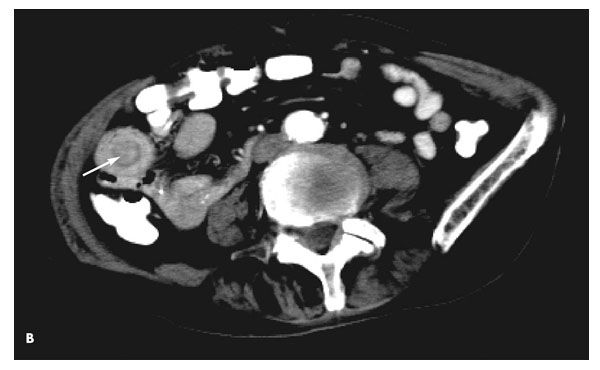

A CT scan of the abdomen and pelvis with contrast revealed a 2-cm ileo-ileal intussusception in the right abdomen without small-bowel obstruction or visualized mass (A). No free air, ascites, or acute inflammatory changes were identified.

Adults usually present with intermittent colicky abdominal pain, nausea, hematochezia, and vomiting. Abdominal imaging confirms the diagnosis. Abdominal radiographs are not useful unless there is perforation or significant obstruction, which is rare in adults (less than 1% of all cases). Axial CT scans show the classic target sign of bowel within bowel (B, arrow). Barium studies show a coiled-spring appearance from the trapping of contrast between the portions of bowel.1